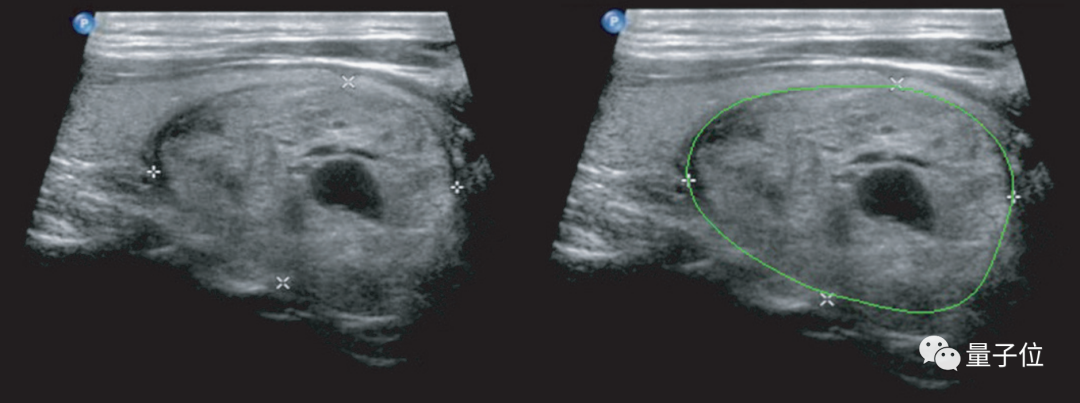

****△使用深度學習進行的甲狀腺結節檢測和定性診斷(右)

這種AI輔助診斷的準確度,當時就已經比中國甲等醫院的放射科醫生至少高出10%。